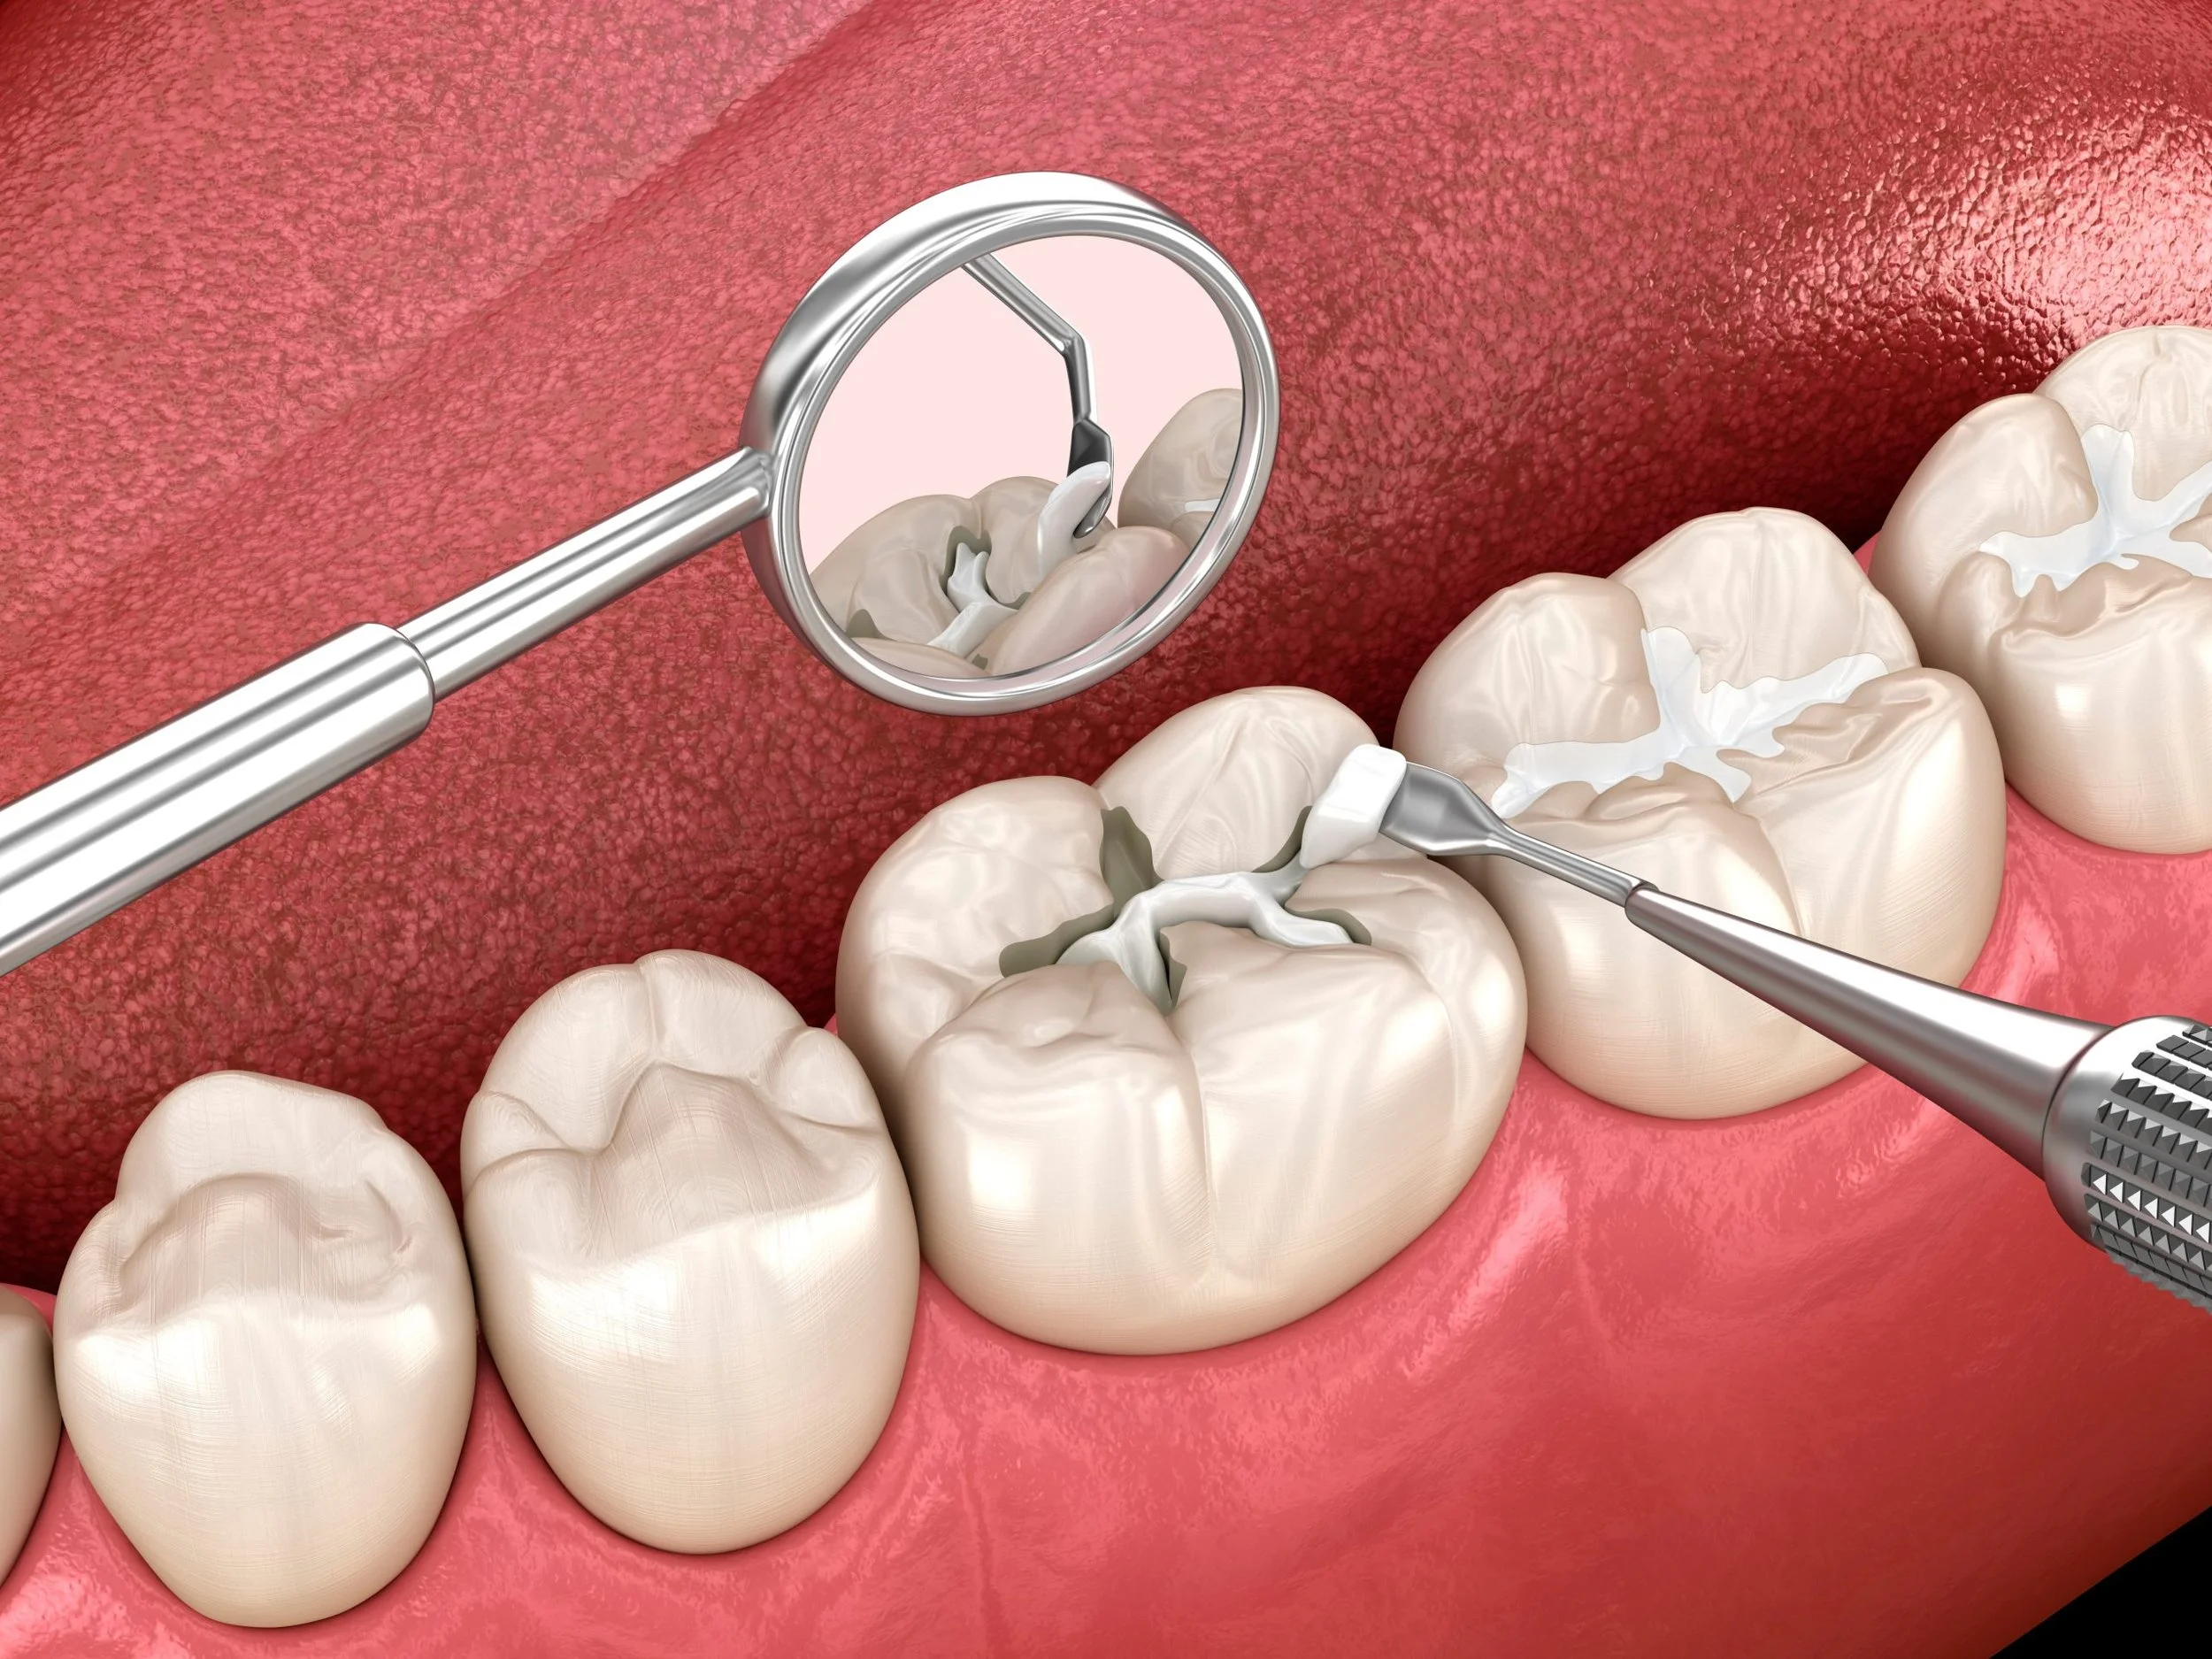

Resinas

Las resinas dentales son restauraciones estéticas que permiten reparar caries, fracturas o desgastes, devolviendo la forma, función y apariencia natural del diente de manera rápida, segura y conservadora.

Selladores

Los selladores dentales son una capa protectora que se aplica sobre las superficies de los molares para prevenir la aparición de caries, especialmente en niños y adolescentes. Es un procedimiento rápido, indoloro y altamente preventivo.